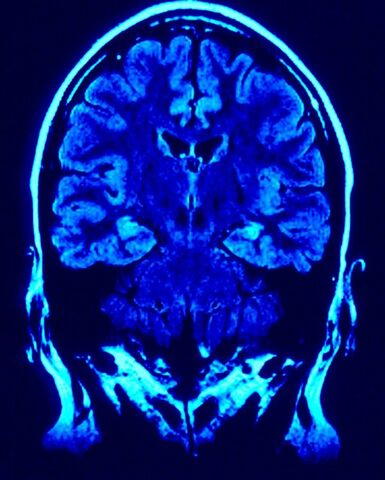

• Neuropsicologia.

Es conocida actualmente como la conexión directa que hay entre el cerebro y la conducta, ya que, la personalidad puede ser modificada si se sufre una lesión en el cerebro, aunque esto depende mucho de la zona afectada, por ejemplo el caso del accidente de Phineas Gage que con el paso del tiempo su personalidad fue cambiando después de haber sufrido el accidente.